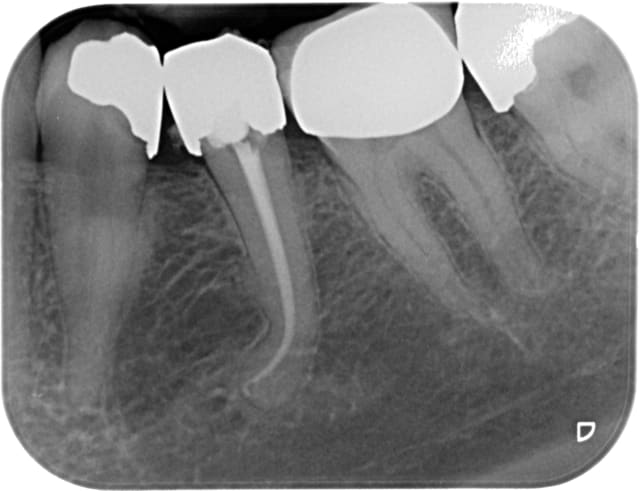

Tout est évidemment nécrosé, et donc aucune constriction sauf étrangement en D. J'y suis donc allé au sonar électronique.

Aucun symptôme, pas de suintement, faible saignement au bout des cônes de papier dont je suis venu à bout avec 3 ou 4 sachets de 5 cônes.

Maître cône ajusté sur donnée du magnifique localisateur Joypex 5, c'est-à-dire coupé la gutta au bout pour que ça colle à la longueur électronique.

Et thermocompacteur en restant à 5 mm de la LT

Il y a l'air d'y avoir un cône en M (j'aimerais croire que ce n'est que de la pâte), peut-être aurais-je dû donner un coup de finger spreader avant pour bien écraser et mouler le cône.

Et une compression au fouloir à amalgame de gutta sur le plancher pour compresser de la pâte sur des canaux accessoires du plancher, ici apparemment absents.

Temporisation à l'IRM.

Étrange la forme en distal de la racine distale..

Il n'y a rien d'étrange, c'est juste une résorption externe provoquée par la lipoe.